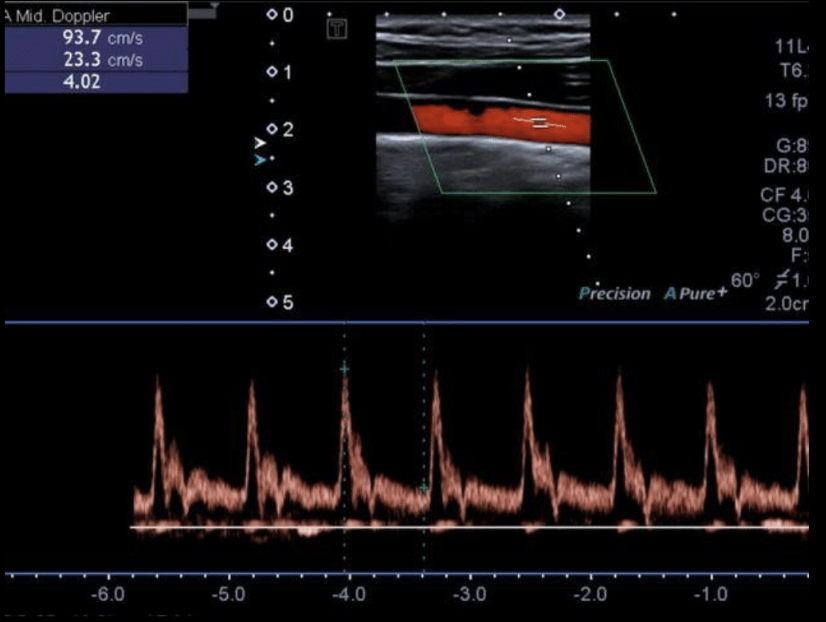

¿Cómo se le llama a la onda normal del flujo?

Trifásica

Factores que afectan el aspecto de las ondas

Contracción cardiaca

Distensibilidad vascular (estenosis)

Resistencia vascular (remificaciones)

x = tiempo (segundos)

y = velocidad (cm)

positivo = por encima de la línea

negativo = por debajo de la línea